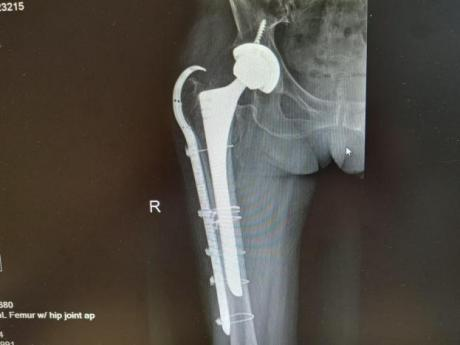

为提升区域内基层医疗机构糖尿病足诊疗服务能力、促进青年医师对糖尿病足的规范化诊治水平,遵义市第二城市医疗集团总院(贵州航天医院)圆满举办贵州省继续医学教育项目——胫骨横向骨搬移技术治疗糖尿病足专题研讨班。 贵州航天医院党委委员、副院长彭亮出席会议并致辞,遵义市第二城市医疗集团各成员单位,以及红花岗区、汇川区、绥阳县、桐梓县等多个区县的基层医疗机构骨干医师参加会议。 研讨班 本次研讨班以胫骨横向骨搬移技术在糖尿病足治疗中的应用为核心主题,围绕糖尿病药物治疗与生活方式管理策略、围手术期血糖精准调控要点、胫骨横向骨搬移技术典型病例深度解析、糖尿病足的临床分型与个体化治疗方案制定等临床实践中的热点与难点展开深入探讨,通过专题授课、案例研讨、互动交流等多元化形式,为参会者搭建了理论与实践结合的学习平台。 此次研讨班不仅为区域内基层医院搭建了学术交流与经验共享的平台,更对推动糖尿病足预防、诊断与治疗的规范化、系统化发展起到了积极作用,有效助力青年医师更新专业知识体系、提升临床技能,为进一步保障区域内糖尿病足患者的健康奠定了坚实基础。 贵州航天医院骨科专家简介 陈明勇 骨一科主任,副主任医师 临床擅长:从事创伤骨科工作约20年,对骨缺损、骨不连、骨肿瘤、肢体畸形等的肢体矫形重建及功能重建,慢性化脓性骨髓炎的根治治疗、糖尿病足的保肢治疗、快速康复理念(ERAS)下的老年骨折的诊治,四肢复杂骨折的诊治,四肢骨折等微创手术治疗具有丰富的临床经验。 2004年毕业于遵义医学院临床专业,曾在中国人民解放军总医院、广西医科大学第一附属医院、上海第六人民医院骨科进修。中国中西医结合学会骨伤科专业委员会横向骨搬移治疗糖尿病足及微血管网再生学组首届委员,遵义市医学会创伤分会常务委员。 瞿 晖 骨科党支部书记,骨二科主任,副主任医师 临床擅长:对骨科的常见病、关节外科、脊柱外科及运动医学疾病的诊治具有丰富的临床经验,熟练掌握骨科手术操作技术。 毕业于遵义医学院临床医学系,2005年前往广州中山大学第一附院骨显微医学部进修学习,2011年前往成都华西医院进修学习,并多次在省内外学习骨科相关知识,是中华医学会骨科分会会员。 赵小锋 中共党员,骨二科副主任,副主任医师 临床擅长:从事骨科临床工作11年,对骨科常见病、多发病诊疗有较为丰富的临床经验,擅长脊柱相关疾病诊断及治疗,尤其是颈、腰、腿疼痛疾病诊断及治疗,擅长胸腰椎骨折微创经皮穿刺内固定术、经皮穿刺椎体成形术、经皮穿刺脊柱内镜下腰椎间盘摘除术、单纯开创腰椎间盘摘除术、腰椎滑脱复位椎间植骨椎融合内固定术、腰椎管狭窄减压融合内固定术及人工髋、膝关节置换术等。 2012年毕业于遵义医学院外科学专业硕士研究生,2019年参加“遵义市115医学人才精英计划”于上海交通大学第一附属医院培训学习,2023年于北京大学第三人民医院脊柱外科进修学习,曾获得遵义市优秀医师荣誉称号。 遵义市手外科第一届委员,遵义市医学会创伤分会第一届委员,遵义市医学会创伤分会第二届委员,贵州省康复医学会第三届脊柱脊髓专业会委员,遵义市医学会烧伤与整形外科学分会委员,发表论文5篇,其中国家级核心期刊1篇,SCI论文1篇,主持市级课题1项并结题,参与市级课题2项。 赵兴东 骨科主任医师 临床擅长:擅长骨科的常见病及各种创伤、四肢骨折创伤修复、骨感染、手足疾病的诊治和手足体表畸形的矫形整复,熟练掌握骨科四肢骨病及创伤的手术操作技术,尤其在四肢关节复杂性损伤、手足外伤、组织缺损创面、难治创面的皮瓣修复方面及平足、高弓足矫形方面及四肢慢性疼痛诊治、康复方面具有丰富的临床经验。 硕士研究生,毕业于遵义医学院临床外科系,2015年前往山东省立医院手足外科进修学习;遵义市医学分会创伤分会第一、二届委员,遵义市手外科医学会第二委届员会常务委员;在省级及省级以上期刊发表文章9篇,参编著作2部,参与主持并完成市级课题1项,参与市级课题2项、省级课题1项。 张艳金 中共党员,骨科副主任医师 临床擅长:从事骨外科工作16年,对复合伤、多发伤的救治、四肢骨干骨折、关节周围骨折、骨肿瘤、骨髓炎等诊治具有丰富的临床经验。 中共党员,硕士研究生,2006年本科毕业于山西医科大学第二临床医学院,2011年研究生毕业于北京军区总医院;在“老年COPD患者合并髋部骨折的诊治”国际合作课题组研究两年,在老年髋部骨折的诊治方面具有丰富的经验,并发表论文6篇;主持遵义市级课题1项,承担遵义医科大学的临床教学工作,获得遵义医科大学优秀带教老师荣誉。编撰有《骨科疾病诊疗精粹》一书,开展2项新技术,编撰地方规范《务川自治县创伤骨科常见疾病诊疗规范》一书。 张俊凯 骨科副主任医师 临床擅长:从事骨科临床工作28年,对创伤骨折、骨感染、骨缺损、骨不连等外科诊治,四肢骨折的微创手术治疗,四肢复杂骨折(如关节内粉碎性骨折、多发骨折等)的损伤控制及手术治疗等具有丰富的临床经验。 1995年毕业于遵义医学院临床专业,2009年前往复旦大学附属医院骨科进修1年。 卢懿明 中共党员,骨科副主任医师 临床擅长:从事骨科工作18年,对创伤骨折、四肢骨折的微创手术治疗、四肢复杂骨折(如关节内粉碎性骨折、多发骨折等)的损伤控制及手术治疗,尤其是髋部骨折的PFNA等微创技术,踝关节骨折、膝关节周围骨折的Mipo微创技术等具有丰富的临床经验,开展了4项新技术,发明6项新型专利技术。 2005年毕业于遵义医学院临床专业,2017年,前往南方医科大学第三附属医院骨科进修半年,回院后运用Mipo技术对骨干骨折及干骺端骨折的治疗技术,同时积极开展骨盆骨折、髋臼骨折腹直肌外侧切口的应用;发表了多篇专业论文,经常参与省内外学术交流会授课,获得医院荣誉称号多个。 邬夏荣 骨科副主任医师 临床擅长:从事骨科工作16年,对四肢复杂骨折、骨肿瘤的诊治,尤其是足踝创伤、慢性踝关节损伤、平足症等诊疗具有丰富的临床经验。 2006年毕业于遵义医科大学临床医学专业,曾在陆军军医大学西南医院进修学习,发表多篇骨科学术论文。 余德怀 中共党员,骨科副主任医师 临床擅长:从事骨科工作10余年,对运动医学、骨关节、脊柱外科常见病、多发病的诊治具有丰富的临床经验。 硕士研究生,2011年毕业于遵义医学院临床医学专业,曾前往遵义医科大学附属医院运动医学专业进修学习;是贵州省医学会运动医学分会青年委员,西部关节镜联盟委员;发表多篇骨科学术论文。 冯 乾 骨科副主任医师 临床擅长:从事骨科工作近20年,熟练掌握骨科多发病及常见病的诊治,尤其对脊柱退变性疾病的诊断及治疗具有丰富的临床经验,主要研究脊柱微创相关治疗方式,能熟练开展椎间孔镜及UBE。 曾前往北京大学第三医院进修学习疼痛及椎间孔镜、首都医科大学友谊医院专业进修脊柱内镜;是贵州省康复医学会第三届脊柱脊髓专业委员会委员;发明专利3项、发表脊柱外科专业论文多篇。 贵州航天医院骨科简介 基本情况 贵州航天医院(原3417医院)骨科组建于1968年,前身是以创伤和断肢(断指)再植闻名于世的上海市第六人民医院骨科,中国断肢(断指)再植的奠基者、中科院院士陈仲伟等专家莅临科室指导医疗和教学,并在70年代开展了贵州省首例断肢(断指)再植手术。组建50余年来,诊治患者已逾百万,挽救了无数的伤病员,成为了保障遵义地区人民群众健康的重要支撑。 经过几代人的不懈努力,今天的骨科,已由创伤骨科发展至骨病、骨肿瘤、骨结核等领域,现有脊柱外科、关节外科、四肢创伤、手足外科四个亚专科,成为了集医疗、教学、科研于一体的综合学科,是贵州省临床重点专科、遵义市临床重点专科、遵义市骨科临床医学中心、遵义市基层骨科专科联盟理事长单位。 科室目前开放床位110张,共有医护人员50余人,副高级以上专家18人,硕士研究生15人。拥有一流骨科医疗设备多台,每年不定期选派优秀技术骨干到全国各大知名医学院校进修、学习、参观、交流,并邀请国内、国外知名专家教授来院进行交流、指导,通过不断引进国内外先进的诊疗技术,科室医疗技术水平稳步提升,为广大人民群众提供了优质的医疗服务。 专科特色 骨一科 (一)骨缺损、骨不连的肢体与功能重建 胫骨横向骨搬移技术治疗糖尿病足: (二)慢性骨髓炎的根治治疗 (三)肢体缺血性疾病如糖尿病足、脉管炎的保肢治疗 (四)皮瓣修复 (五)复杂创伤的治疗 (六)老年髋部骨折及小儿骨折快速手术 老年髋部骨折: 骨二科 (一)胸腰椎骨折微创经皮椎弓根螺钉固定术 (二)老年性骨质疏松性患者腰椎滑脱脊柱内固定术(骨水泥螺钉) (三)V形双通道脊柱内镜技术(VBE)腰椎融合术治疗腰椎退行性疾病 (四)老年性骨质疏松性骨折(PVP/PKP)术 (五)人工髋关节置换术 (六)双侧股骨头坏死人工全髋关节置换 (七)右侧全髋置换术后假体周围骨折翻修 (八)人工膝关节置换术 (九)人工膝关节假体松动翻修 (十)关节镜技术 传统手术切口 关节镜技术切口 诊疗范围 骨一科 1.四肢创伤、矫形。 2.手、足踝外科。 骨二科 End